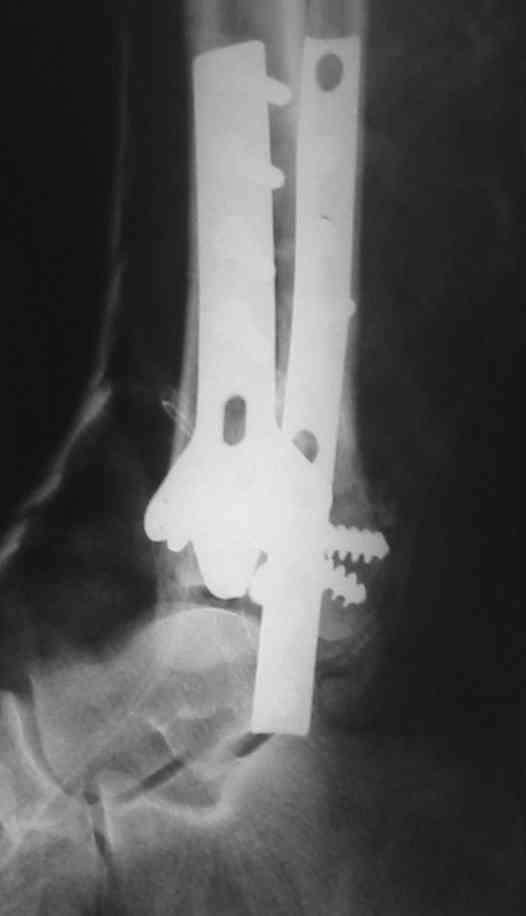

Ja operiroval bolnogo po Vashemu, hotia sam ni ochen' ubezden' v itom, t.k. bolnoi otkazalsa na proch' ot ex.fix, ja emu sdelal ORIF + Kostnia plastika, snimky prelogiottsa,